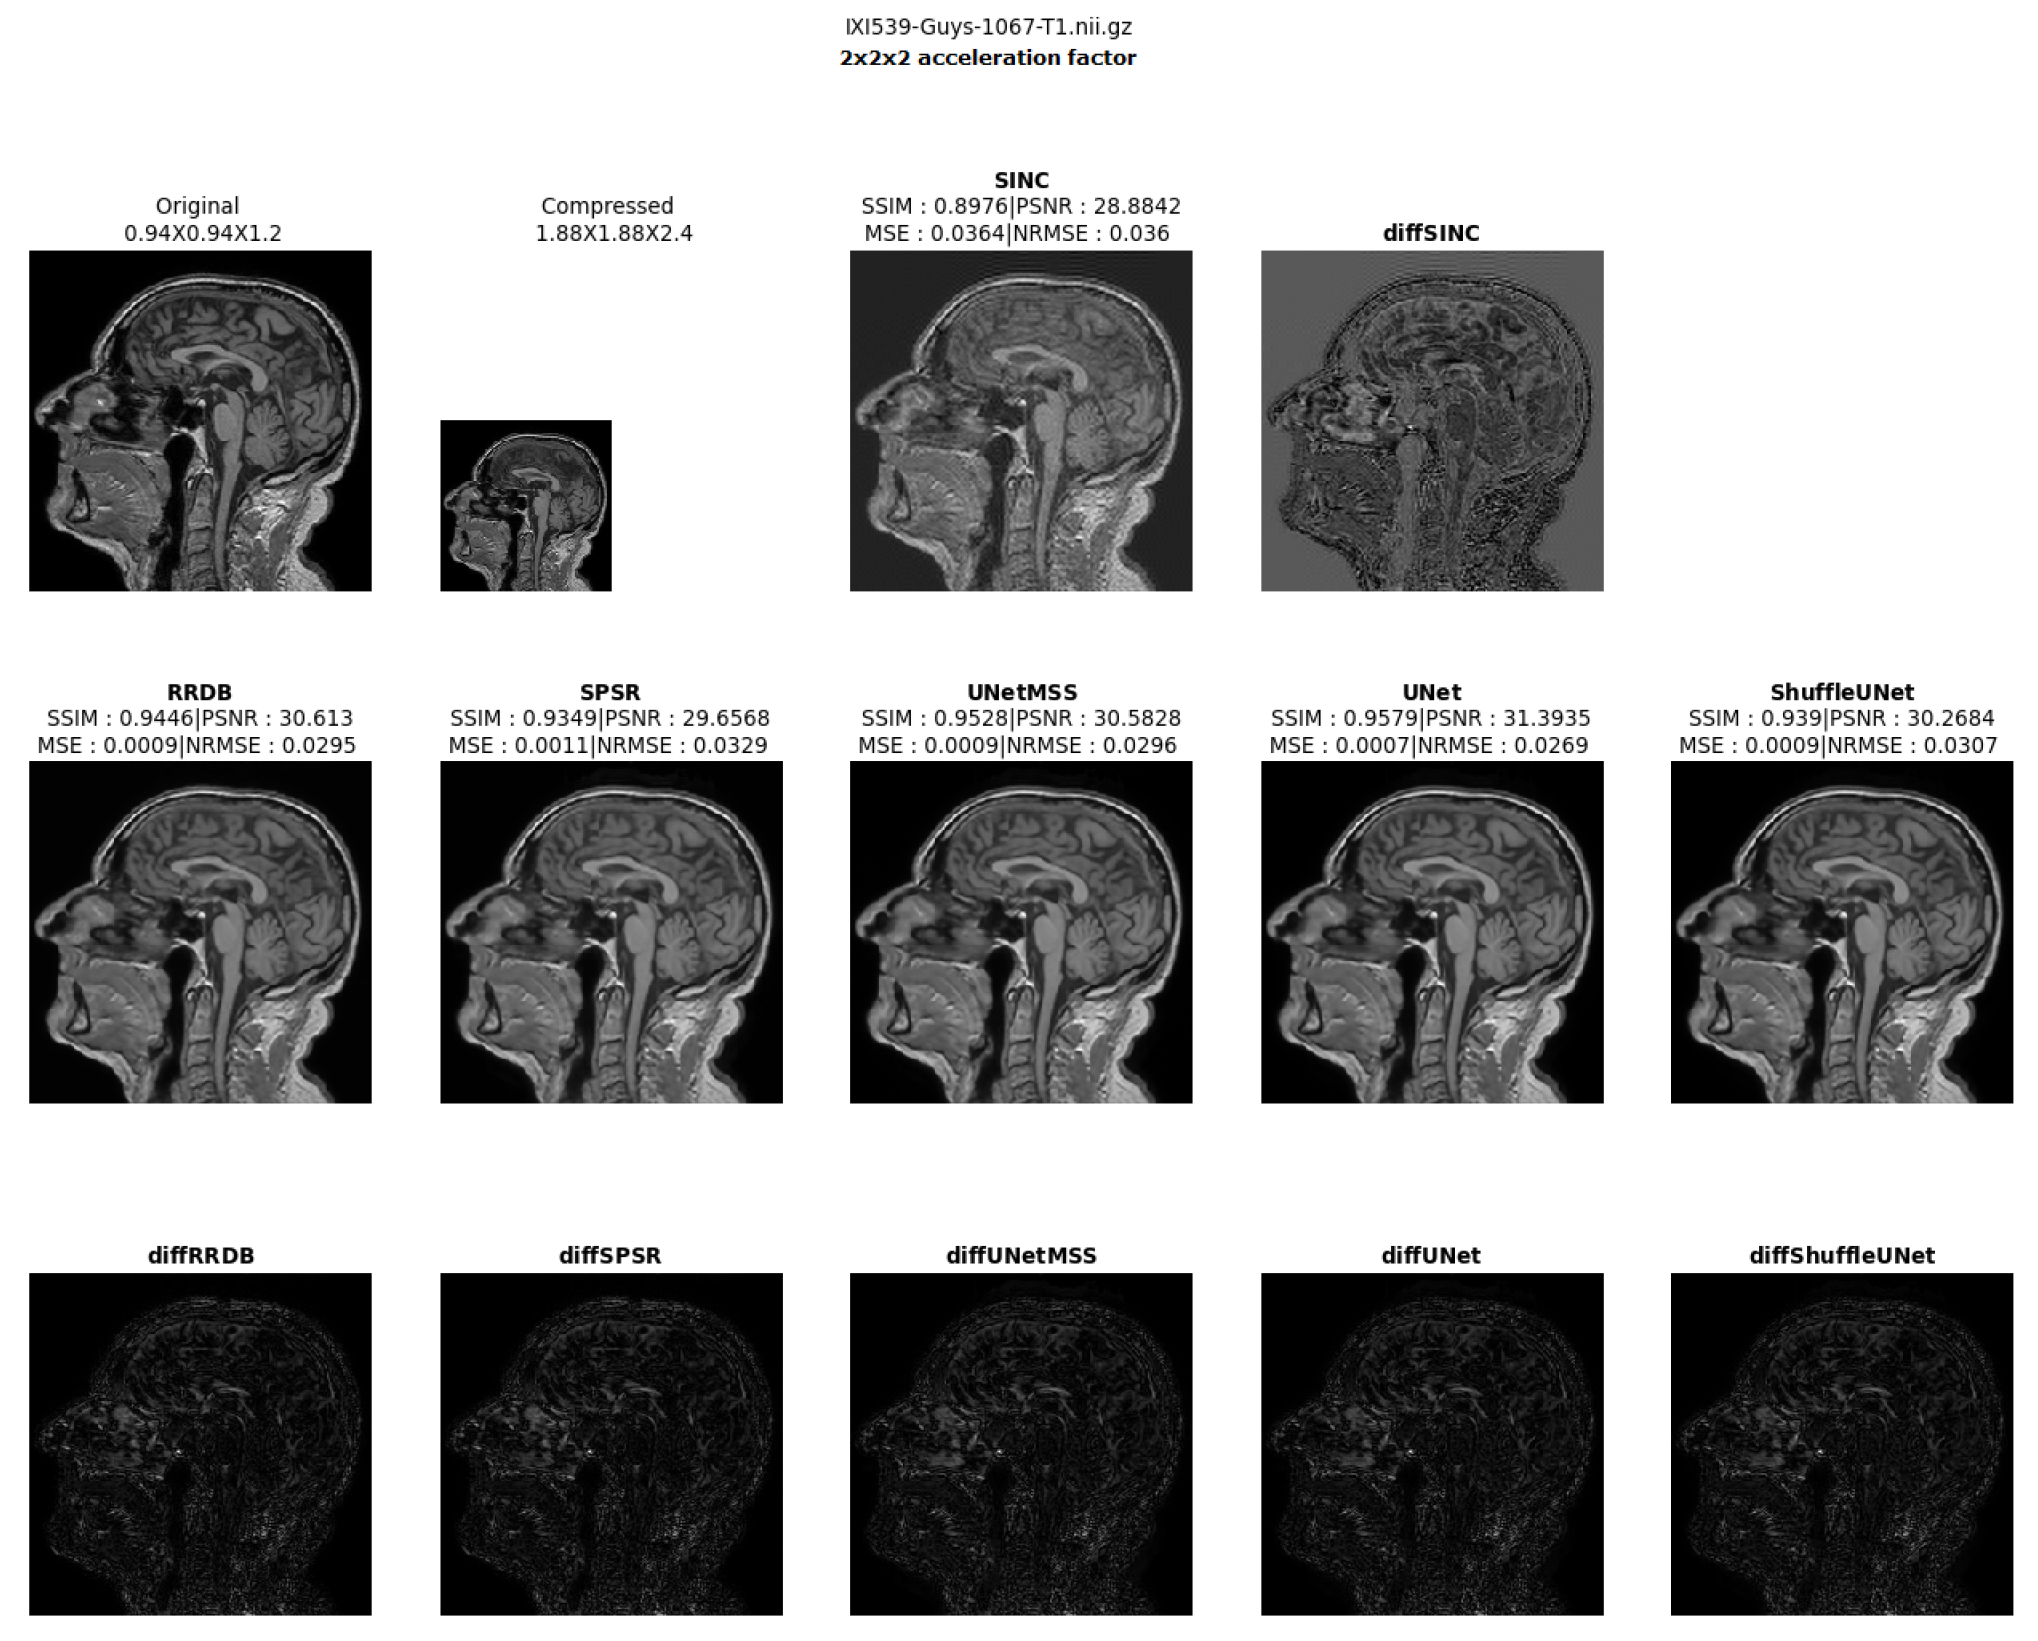

- Visualising individual model results for all the acceleration factors.

Different 3D CNN Models Results Comparison for Cross Acceleration Factor of IXI-T1 Dataset